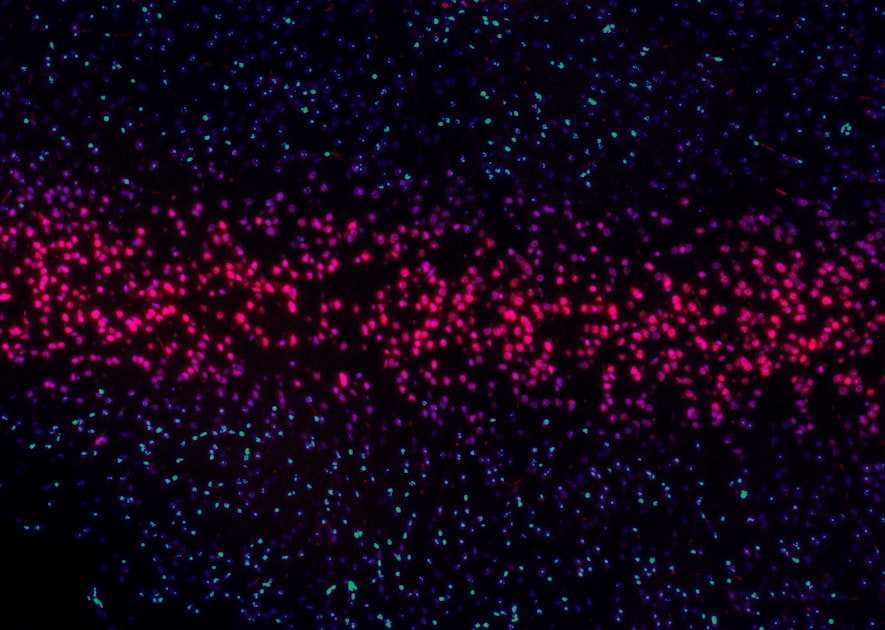

Digital imaging techniques are essential in biomedical research, providing high-resolution images that aid in the understanding of complex biological systems.

These techniques are crucial for developing new drugs and therapies, making them a vital part of the research landscape.